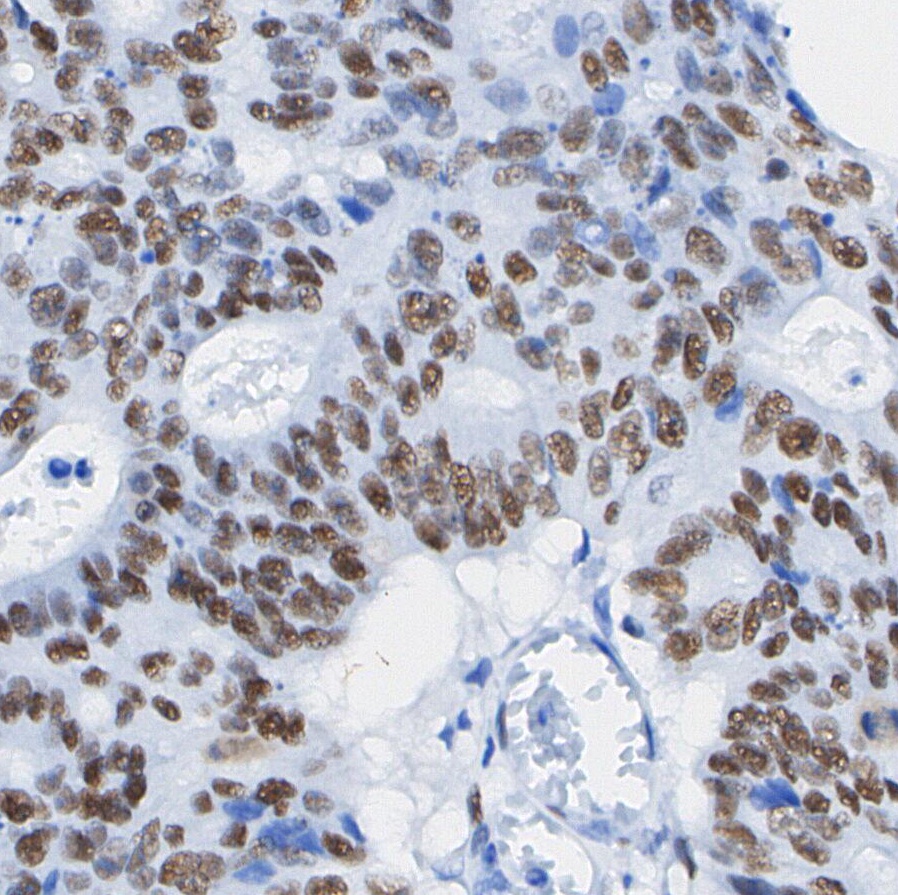

• Immunohistochemical analysis of formalin fixed paraffin embedded human Colorectal cancer tissue with F0451 at 1/200 dilution.